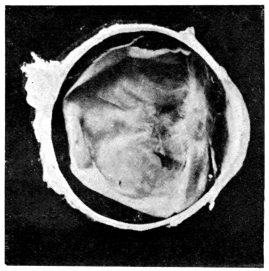

PLATE II.

FACING

PAGE

10.

LENS DISLOCATED BETWEEN CILIARY BODY AND SCLERA

curly bracket span

38

11.

NUCLEUS OF CATARACT FREELY MOVABLE BETWEEN THE AQUEOUS AND VITREOUS CHAMBERS

12.

LENS IMPACTED IN ANGLE OF ANTERIOR CHAMBER

13.

CAPSULE OF MORGAGNIAN CATARACT IMPACTED IN ANGLE OF ANTERIOR CHAMBER

14.

LENS FLOATING FREE IN VITREOUS CHAMBER

15.

LENS LIGHTLY IMPRISONED IN EXUDATE INTO VITREOUS CAVITY